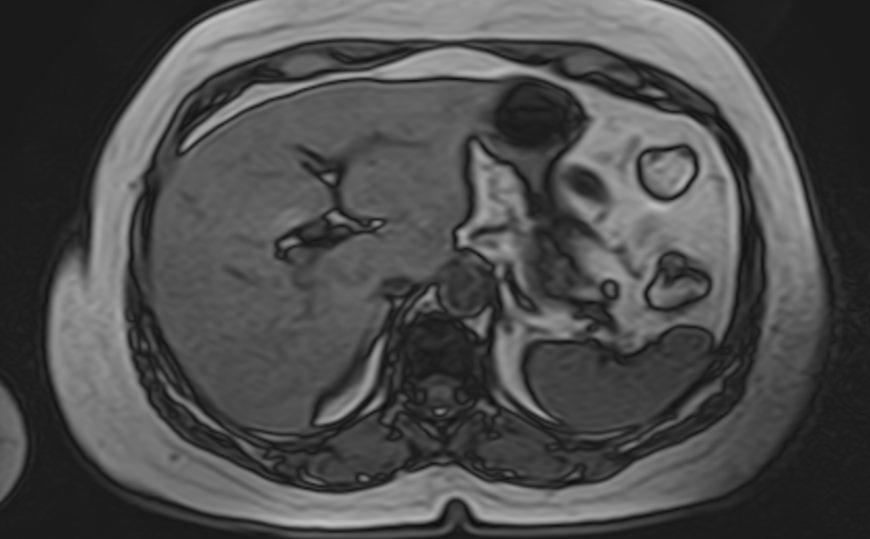

Современным методом обследования для диагностики заболеваний поджелудочной железы является магнитно-резонансная томография. В клинике «Доступная медицина» МРТ поджелудочной железы проводится на новейшем высокопольном томографе экспертного уровня TOSHIBA VANTAGE TITAN 1,5 Тесла, который позволяет получать послойные изображения исследуемой зоны с высокой степенью разрешения. Для лучшей визуализации и выявления минимальных изменений в органе применяется контрастное усиление путем внутривенного введения гадолиниевого контрастного препарата (Магневист, Гадовист, Омнискан и др).

С помощью компьютерного моделирования аппарат создает объемные изображения превосходного качества. Возможности аппарата позволяют поставить точный и достоверный диагноз, что дает возможность выявлять заболевания на ранних стадиях и назначать своевременное лечение.

В процессе МРТ поджелудочной железы получают серию снимков органа, по которым можно оценить следующие параметры:

МР-томография выступает уточняющим методом диагностики при сомнительных результатах УЗИ. Процедура позволяет определить характер, локализацию и масштабы патологического процесса.

Метод применяют при подозрении на онкологический процесс для первичной дифференциации доброкачественных и злокачественных опухолей. Подробные сведения об анатомии поджелудочной железы позволяют исключить осложнения панкреатита. МРТ также применяется для подготовки к хирургическим операциям и контроля результативности лечения.